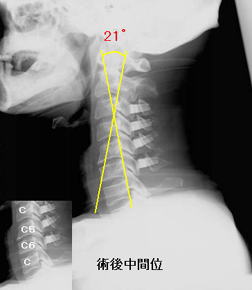

臨床応用例 |

P(パラレル)type/A(アングル)type 適応

P-type |

A-type |

| Alignment |

-5°以下 |

-5°以上 |